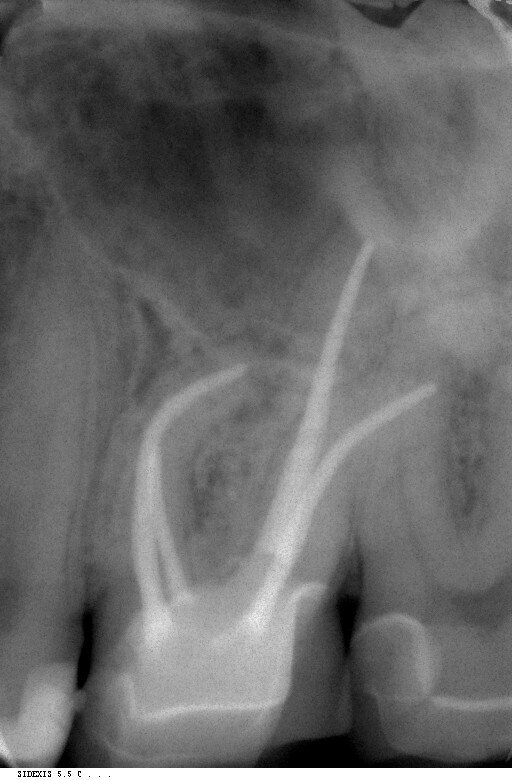

Fig.1: Inital situation.

A 36-year-old patient presented with acute pain in tooth #26 to our practice in October 2012. Radiographic diagnostics showed a deep carious defect distally (Fig. 1). On the basis of these clear findings, we recommended a root canal therapy. The patient agreed to the treatment. After application of the rubber dam, the affected tooth was first built up with composite for greater stability, and then a diamond drill was used to create the appropriate access. The pulp chamber was then opened. All crown pulp tissue was removed from the infected tooth in the process. Canal clearance was checked with a 10/.05 glide path file.